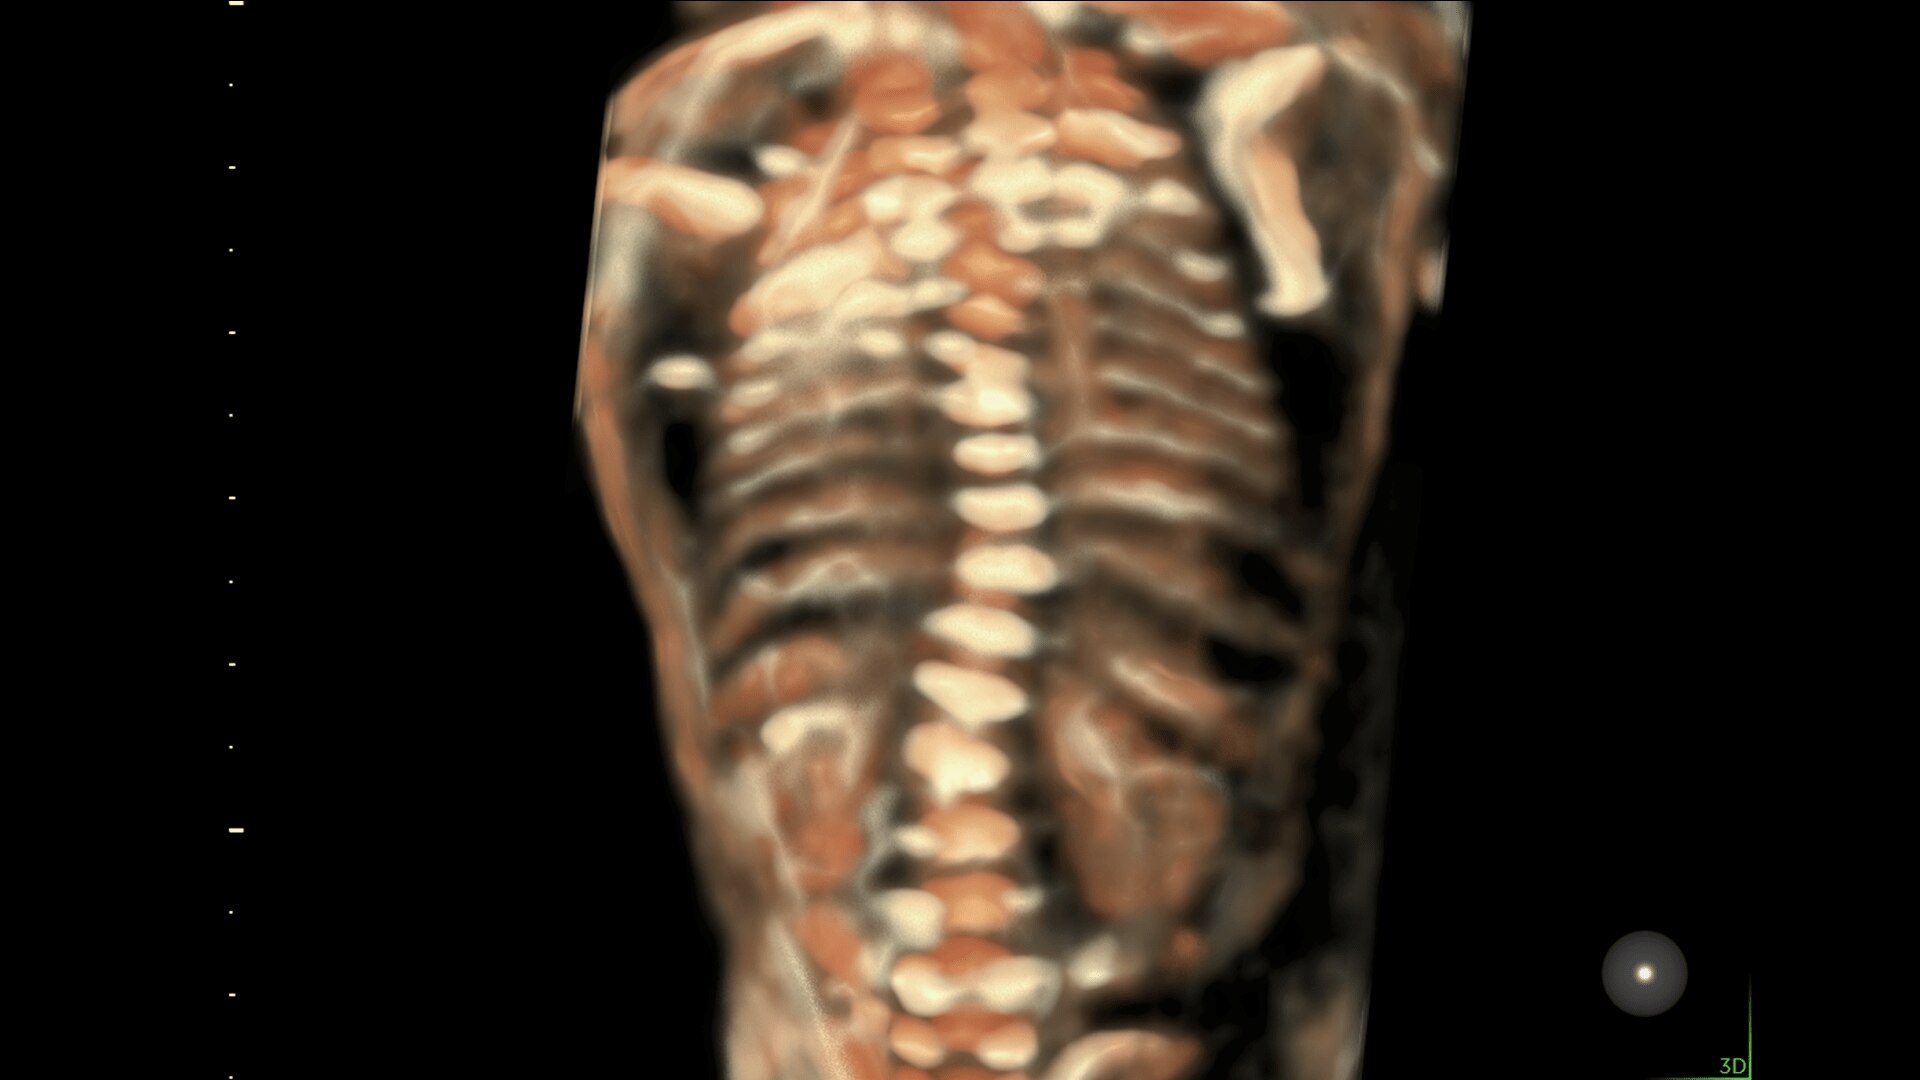

Enhanced Volume Imaging

Deliver next generation 3D/4D & Color images with HDlive Studio+

Obtain high resolution images with advanced probe technology - e M6C, RIC6-12, and RM7C

Super Fine Details

Obtain highly detailed images of the fetal brain, first trimester development, and other complex anatomy with increased axial and lateral resolution.